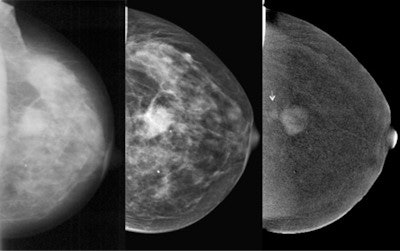

Dr. Carmen Perez Fernandez from the Berlin Charité university hospital shared new data on contrast-enhanced spectral mammography (CESM). This technique requires little more radiation exposure than conventional mammography, but enables the visualization of tissue vascularization. Similar to breast MRI, intravenous contrast-agent injection is necessary, but in the case of CESM, iodinated contrast agent is used. In a study of 118 patients, the sensitivity of CESM reached 78%, whereas specificity was still moderate (about 50%). Although the future role of CESM has to be defined in ongoing research, the technique looks particularly promising when breast MRI is not available. Everybody remains curious about the further development of the method.